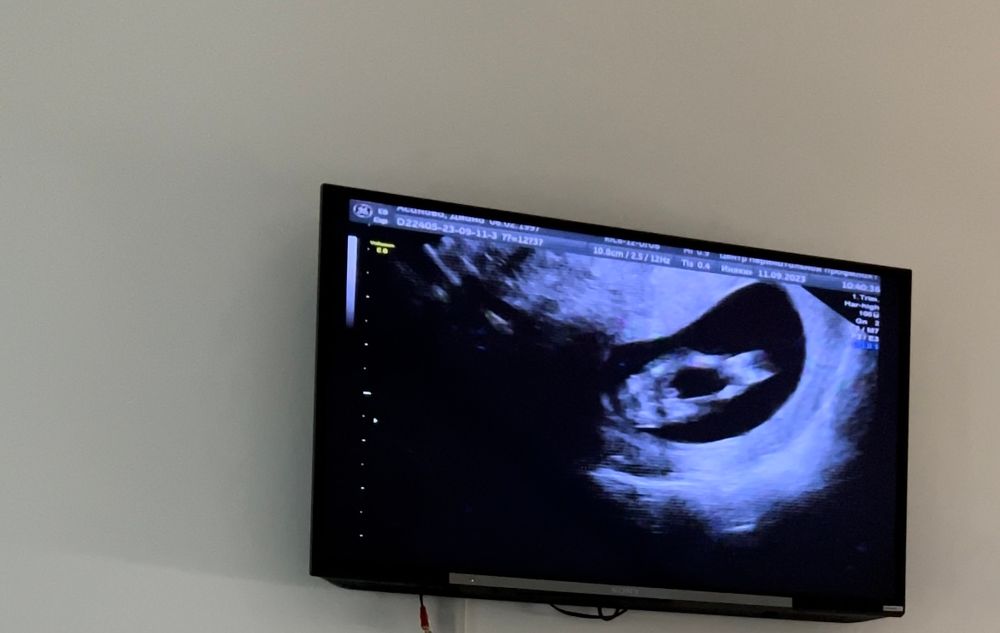

1 скрининг, пол ребёнка и маленький носик

У дочи на этом сроке был носик 1.5, родилась девочка с кнопочкой)) У сына тоже был маленький, но цифр не помню.

Мне потом контрольное узи назначали через неделю, чтобы носовую косточку посмотреть. Через неделю всё хорошо было.

По половом бугорку вроде девочка

Носик у сына был 1.7, а лет мне было 38, но никто ничего не сказал плохого, нос у него теперь просто аккуратный)